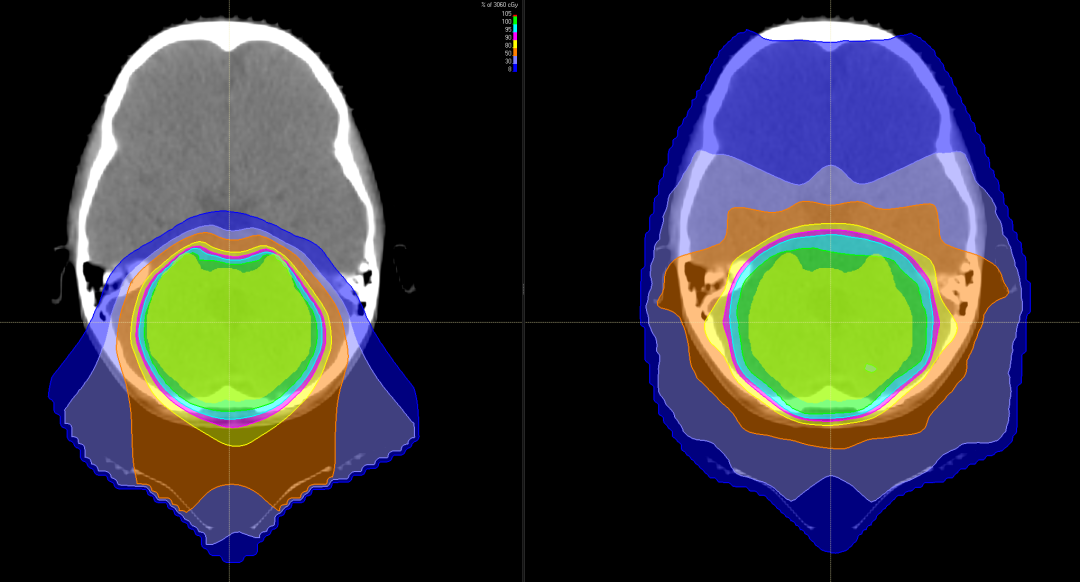

图中患者的脑部扫描显示质子(左)如何专门针对肿瘤,而对周围组织和结构的辐射最小,传统的光子辐射(右)会损坏周围的组织和结构。